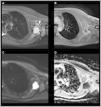

El sarcoma sinovial (SS) es una neoplasia maligna infrecuente del tejido blando adyacente a las articulaciones, siendo el sarcoma de tejidos blandos (STB) de tipo «no rabdomiosarcoma», más diagnosticado en la infancia (30%). Su localización más frecuente es la rodilla y tobillo, representando el STB más común del pie. A diferencia de otros STB, presenta un crecimiento lento y una edad más temprana al diagnóstico (adolescentes y adultos jóvenes), por lo que muchos casos son inicialmente diagnosticados como procesos benignos de forma errónea. La resonancia magnética (RM) es clave para su caracterización, si bien comparte características con otros STB. El diagnóstico definitivo es anatomopatológico, que evidencia la translocación patognomónica t(x;18)(p11;q11) con técnica de hibridación fluorescente in situ (FISH). El objetivo de este artículo, ilustrado con casos diagnosticados en nuestro centro, es resaltar las características claves para el enfoque diagnóstico del SS, fundamentalmente mediante el uso de técnicas de imagen radiológicas, así como estudios de medicina nuclear y anatomopatológicos.

Synovial sarcoma (SS) is a rare malignant neoplasm of the soft tissue adjacent to joints. It is the most commonly diagnosed non-rhabdomyosarcoma soft-tissue sarcoma (STS) in childhood (30%). Its most frequent location is the knee and ankle, and it is the most common STS to affect the foot. Unlike other STS, it has slow growth and an earlier age at diagnosis (adolescents and young adults), which is why many cases are initially misdiagnosed as benign processes. Magnetic resonance imaging (MRI) is key due to its characterisation capabilities as SS shares features with other STS. Definitive diagnosis is achieved through a pathological study that shows the pathognomonic translocation t(x;18)(p11;q11) with the fluorescence in situ hybridisation (FISH) technique. The objective of this article is to highlight the key characteristics that are useful for diagnosing SS, fundamentally through the use of radiological imaging techniques, as well as nuclear medicine and pathological studies, illustrated with cases diagnosed in our centre.